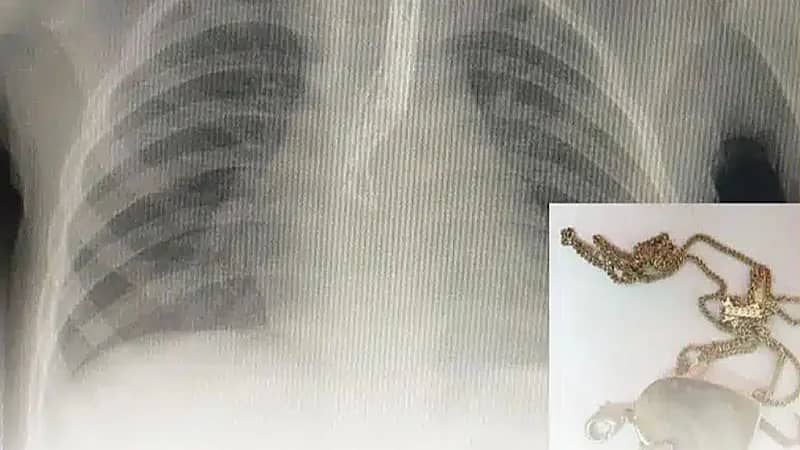

“الفرق الطبية“ تنجح في إنقاذ حياة طفلة ابتلعت “قلادة” بالمدينة المنورة

المدينة المنورة